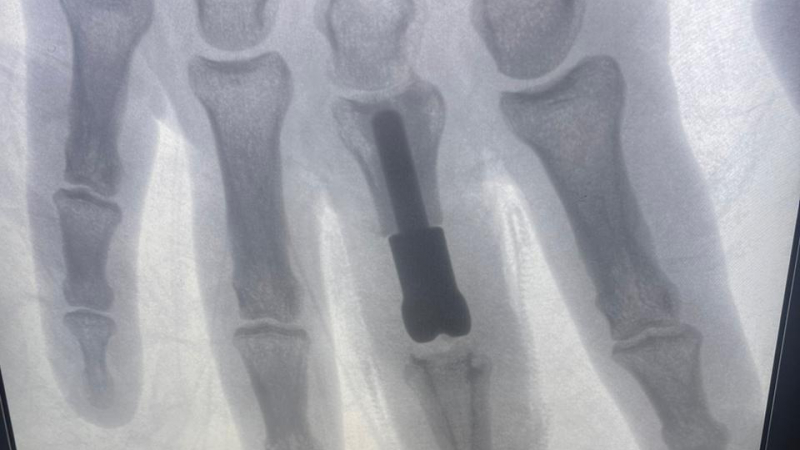

К хирургам-травматологам попал мужчина с открытым оскольчатым внутрисуставным переломом 3 пальца правой кисти. Это тяжелое повреждение, затрагивающее не только кости, но и межфаланговый сустав. Также были травмированы сухожилия, участвующие в разгибании пальца, и покровные ткани.

Такую травму невозможно вылечить стандартными способами (гипсовая повязка, остеосинтез). В случае открытого, мелкооскольчатого перелома, когда восстановить суставные поверхности не представляется возможным, необходима замена поврежденного сустава на протез. Но площадь поражения костей пальцев у пациента была значительной, установка стандартного эндопротеза привела бы к укорочению пальца и неудовлетворительному окончательному результату. А это, напомним, правая, доминирующая рука.

Врачи пришли к решению о необходимости изготовления индивидуального эндопротеза, который смог бы заменить не только сам сустав, но и восполнить дефект основной фаланги пальца.

«Протез, высокотехнологичный имплант, был изготовлен с применением аддитивных технологий. Если мы привыкли, что традиционно детали изготавливаются путем «вычитания» лишнего материала из заготовки, то в основе аддиктивных технологий, напротив, лежит принцип «добавления». Протез был «напечатан» из титанового порошка на 3d принтере. Полученная конструкция учитывала все малейшие нюансы и особенности, которыми должен обладать имплант, предназначенный для конкретного пациента. В России в настоящее время есть уже несколько биометрических лабораторий, которые занимаются подобной инновационной деятельностью.

За точность размеров компонентов и их форму отвечал биоинженер. Задача хирургов заключалась в установке созданного эндопротеза и проведении пластики поврежденного сухожилия. Операция прошла успешно», – рассказал о проделанной работе хирург-травматолог Алексей Сизиков.